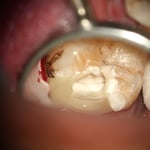

メタルインレー下にはレジンの覆髄が施されていましたが、接着しておらず、ポロリと取れました。これが、2次齲蝕(治療後の虫歯の再発)の原因です。多量の軟化象牙質(虫歯)を除去していくと、歯髄腔(神経と血管が入っている部屋)まで紙一枚。うっすら赤い血流も確認できます。齲蝕除去中に口蓋側の咬頭が破折しましたので、グラスファイバーポストによって、生活歯の支台築造。神経も取らずに残せる歯は、本当に多くあります。